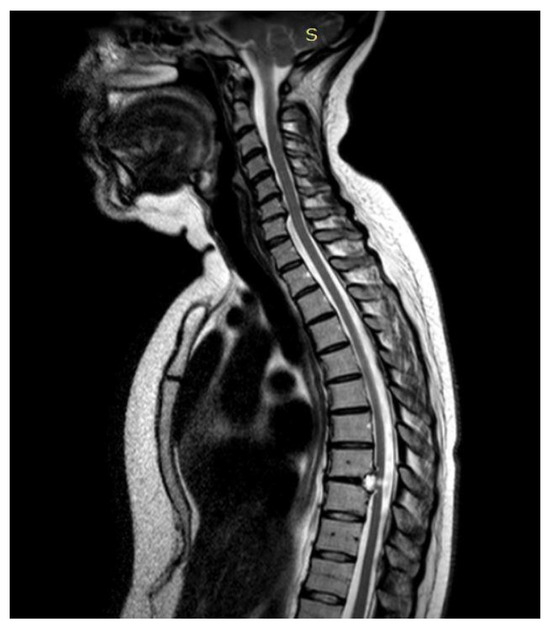

3.4.3. Case 3

3.4.4. Case 4

3.4.5. Case 5

| Level | T12–L2 | C5–C6 | T7–T10 | T8–T9 | T8–T11 |

| Location | Intramedullary | Intradural | Intradural–Extradural | Intramedullary | Intradural |

| Primary/secondary | Secondary | Secondary | Secondary | Secondary | Secondary |

| Surgical treatment | lysis of adherences and syrinx cavity opening | resection of the cystic formation and adhesiolysis | resection of the cystic formation and adhesiolysis | resection of the cystic formation and adhesiolysis | resection of the cystic formation and adhesiolysis |

| Complications | CSF fistula | infection | None | CSF fistula | None |

| KPS pre-op (%) | 70 | 50 | 70 | 80 | 90 |

| KPS post-op (%) | 80 | 50 | 60 | 90 | 80 |

| ASIA score pre-op | C | B | B | C | D |

| ASIA score post-op | D | B | C | C | D |